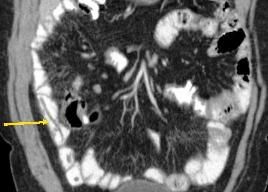

Treatment was initiated with ciprofloxacin and flagyl for a presumed infectious colitis. Because of the cecal findings, the patient was admitted for possible appendicitis. Results of a subsequent CT scan showed large worms in the distal jejunum and ileum (Figures 1-4). Stool samples were sent for an ova and parasite (O&P) test. The patient improved and was discharged home.

Figures 3 and 4